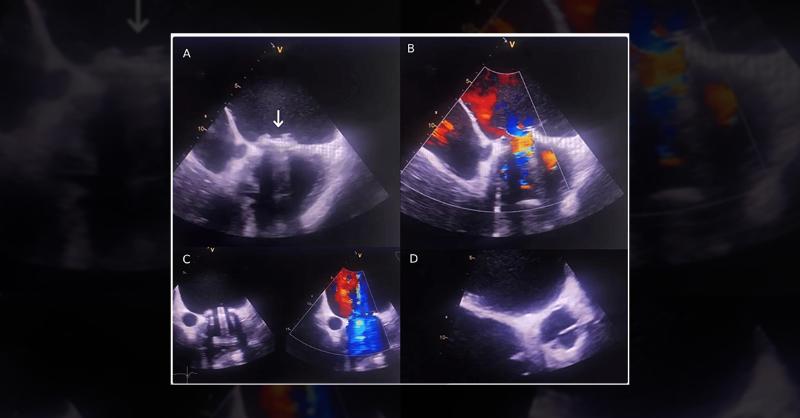

A 68-year-old woman with a history of hypertension and mitral valve replacement was admitted to the intensive care unit (ICU) due to an intracerebral hemorrhage caused by an accidental overdose of oral anticoagulants (1). Her symptoms started 14 days before admission with sudden headaches and altered mental status. A computed tomography scan reveal